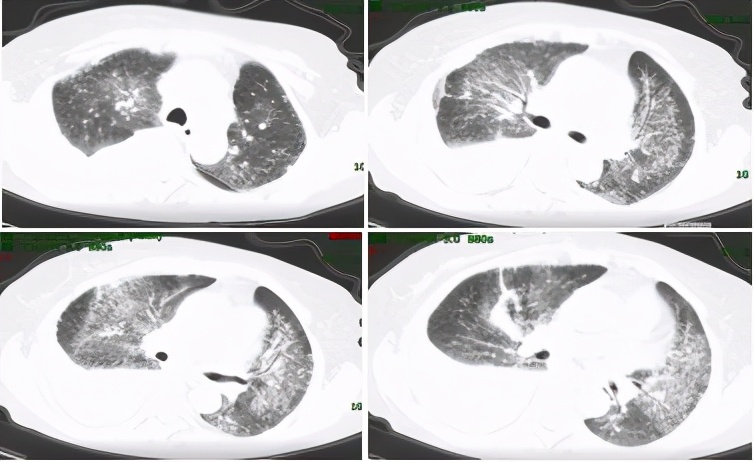

该患者到底是副肿瘤性风湿病综合征,还是肿瘤合并系统性硬化呢?这需要在进一步的治疗中验证。由于该患者及家属不愿行盆腔占位活检,放弃了放化疗等肿瘤相关治疗,因口服激素及复方环磷酰胺后呼吸困难好转,愿意继续行系统性硬化病的相关治疗:泼尼松片(40mg qd,逐渐缓慢减量),复方环磷酰胺片100mg qd (长期口服未减量),乙酰半胱氨酸600mg tid,百令胶囊4颗 tid。经上述治疗后,患者呼吸困难进一步好转,后于治疗后约1个月及3个月后复查胸部CT提示肺部病灶减少,胸水逐渐减少至基本吸收。原则上副肿瘤综合征肿瘤治疗后风湿病表现才明显好转,只是抗风湿治疗好转并不能证明是副肿瘤综合征。通过治疗反应,考虑患者为肿瘤伴发系统性硬化可能性大。

图5:复查胸部CT(2017-03-16)肺部病灶吸收,胸水减少